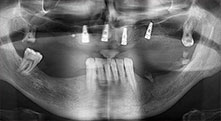

Würden Sie uns kurz beschreiben, wie Sie zum Beispiel beim Mobilisieren von Knochenblöcken für Transplantationen vorgehen?

Bratu: Wir bevorzugen Knochenentnahmen von der Linea obliqua externa des posterioren Unterkiefers, nicht aus der interforaminalen Region. Nach der Weichgewebsinzision verwenden wir die neuen Sägen, um den Umfang der Knochenentnahme zu definieren. Wir erledigen damit in fast 80 Prozent der Fälle auch die gesamte Präparation. Zusätzlich verwenden wir eventuell andere Piezo-Instrumente und zuletzt einen Meißel, um den Block zu mobilisieren. Das ist für uns eine sehr effektive Operationstechnik.

Bratu: Wir augmentieren im seitlichen Unterkiefer gern mit der Sandwich-Technik. Dabei wird ein Knochendeckel mit der Piezosäge präpariert und das krestale Fragment mit Mikroschrauben fixiert. Dazwischen platzieren wir eine Mischung aus autologem Knochen und xenogenem Knochenersatzmaterial. Das funktioniert sehr zuverlässig. Bei Kieferkammspaltungen im Unterkiefer sollten Sie nie auf ausreichend dimensionierte vertikale Schnitte verzichten. Sonst kann der Knochen leicht frakturieren.